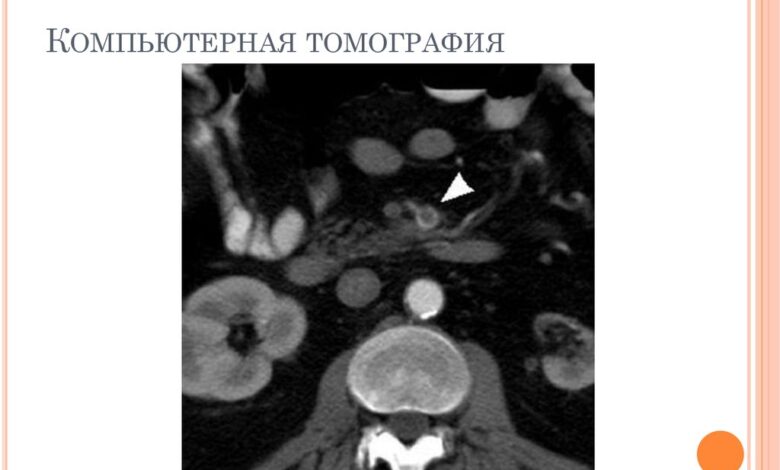

- КТ-ангиография для более детального изучения сосудов с применением контрастного вещества;